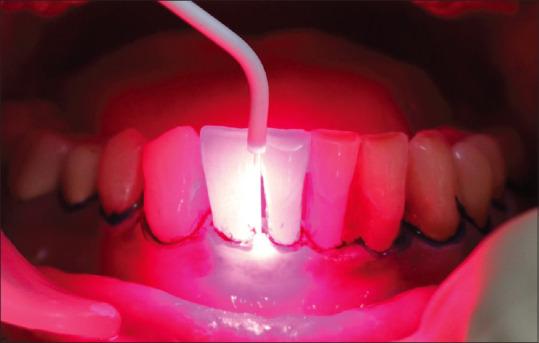

Periodontal disease is considered to be the sixth most common complication of diabetes mellitus (DM). Antibiotics (systemic and local) enhance the outcome of conventional mechanical debridement but frequent use of antimicrobials may develop resistance to microorganisms. To overcome this complicacy, the current study assessed the effectiveness of photodynamic therapy (PDT) in chronic periodontitis patients with type 2 diabetes when used as a combination therapy to standard periodontal therapy by assessing the various clinical and glycemic parameters.

A total of 16 known cases of chronic Periodontitis patients who were suffering from type 2 DM were allocated into two groups. The test group ( = 8) was treated with standard scaling and root planing (SRP) along with PDT while the control group was treated with SRP alone. Various clinical parameters assessed were plaque index, gingival index, pocket probing depth, clinical attachment level, and Glycated hemoglobin level at baseline and 90 days after therapy.

牙周病被认为是糖尿病(DM)第六常见的并发症。抗生素(全身和局部使用)可提高传统机械清创的效果,但频繁使用抗菌药物可能会使微生物产生耐药性。为克服这一复杂性,本研究通过评估各种临床和血糖参数,评估光动力疗法(PDT)作为标准牙周治疗的联合疗法在2型糖尿病慢性牙周炎患者中的有效性。

将1共6例已知患有2型糖尿病的慢性牙周炎患者分为两组。试验组( = 8)接受标准龈上洁治和根面平整(SRP)联合PDT治疗,而对照组仅接受SRP治疗。评估的各种临床参数包括基线时以及治疗后90天的菌斑指数、牙龈指数、牙周袋探诊深度、临床附着水平和糖化血红蛋白水平。